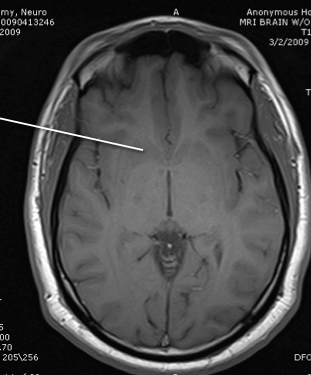

lateral ventricle

posterior horn of the internal capsule

thalamus

anterior limb of the itnernal cpasule